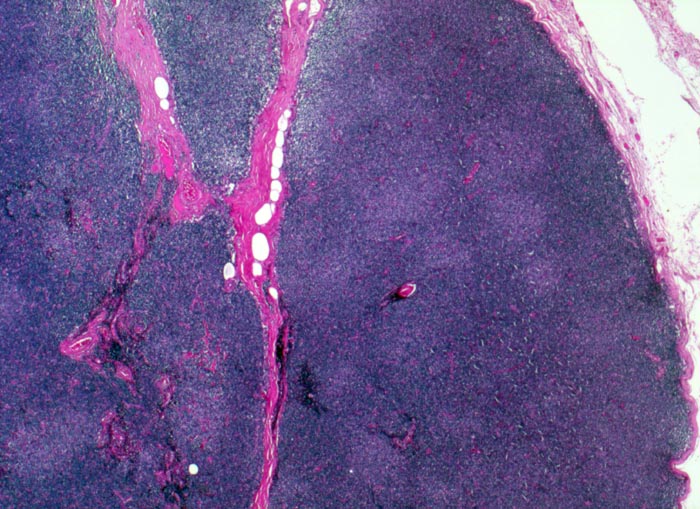

• Vergrösserter Lymphknoten mit zerstörter Lymphknotenarchitektur.

• Diffuse Infiltration des Lymphknotens durch monomorphe kleinlymphozytische Lymphomzellen.

• Unscharf begrenzte helle Areale (Proliferationszentren) auf dunkelblauem Hintergrund.

• Proliferationszentren (=Pseudofollikel) bestehend aus Lymphozyten und Paraimmunoblasten.